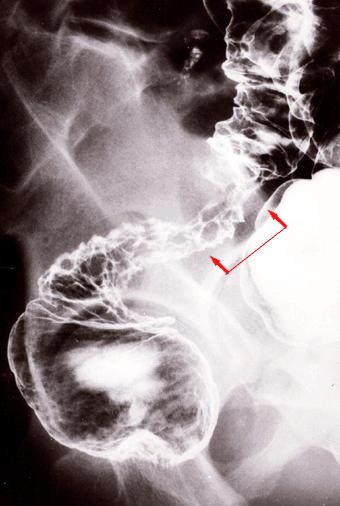

Cáncer Avanzado de Colon de tipo difusamente infiltrado (tipo 4) de Recto - Sigmoides, que se consiguió diferenciar de lesión estenótica de tipo inflamatoria, a partir de sus pliegues gigantes y porciones de mucosa defectuosa en extensiones estrechas

[Image-ID:752]

Tumor Epitelial Maligno/Adenocarcinoma

colon/recto

Rayos X

Tipo 4(Tipo difusamente infiltrado)/

40 -

s(a)